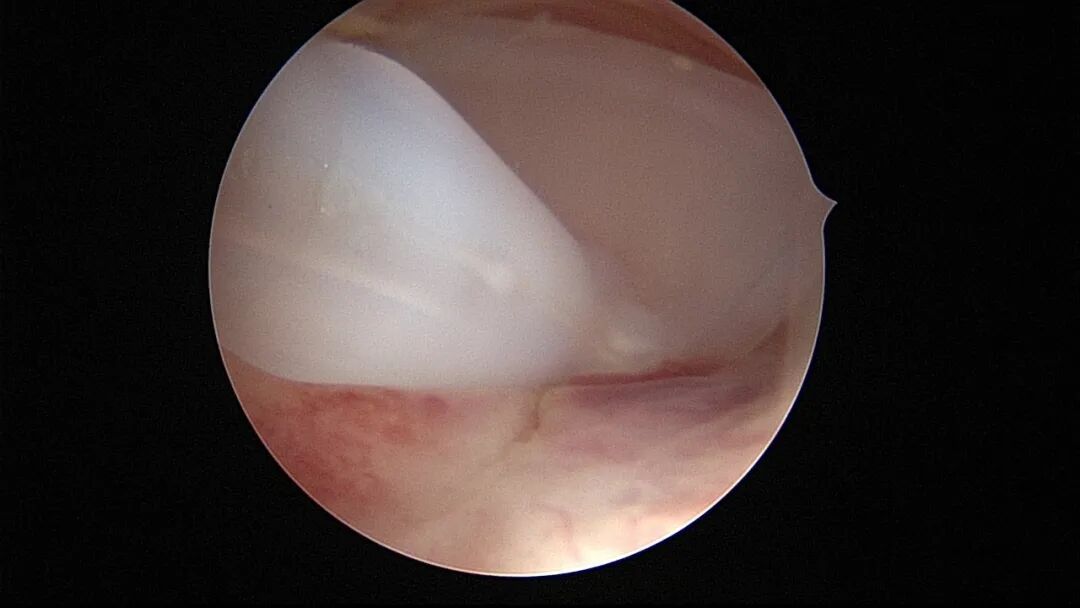

第八次宫腔镜:2025年7月宫腔镜二探取球囊,宫腔形态正常,双侧输卵管开口可见,内膜薄,片状充血。球囊在宫腔具有持续塑形作用,分粘术中没有显露的右侧输卵管开口已自我修复。